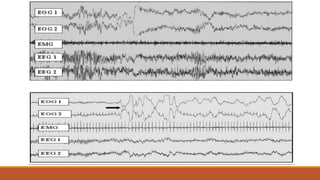

Traçado polissonográfico

Vigília

Sono NREM – Fase 1

CARACTERÍSTICAS GERAIS DO SONO NREM

Fase 01 (N1 – AASM, 2007)

Transição da vigília para o sono.

Consciência ainda está mantida.

Com o fechamento dos olhos, ondas alfa occipitais (8 a 13 Hz na região occipital do crânio).

Ondas teta (4 a 7 Hz).

Movimentos oculares lentos e intermitentes.

EMG mostra redução do tônus muscular.